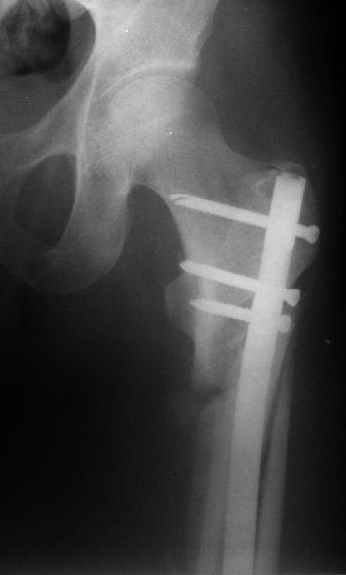

Могу скромно напомнить о существовании стержня нашей модификации.

В частности, на проксимальном конце сделано еще одно дополнительное статическое отверстие. Можно ввести в проксимальном отделе 4 винта, из них 3 статические (2 в круглые отверстия и 1 по нижнему краю овального). Картинки в приложении. На дистальном конце стержня тоже кое-что улучшено. Спрашивайте в аптеках, как говорится. Выпускается предприятием "ЦИТО" (Москва), то есть это малобюджетное решение.